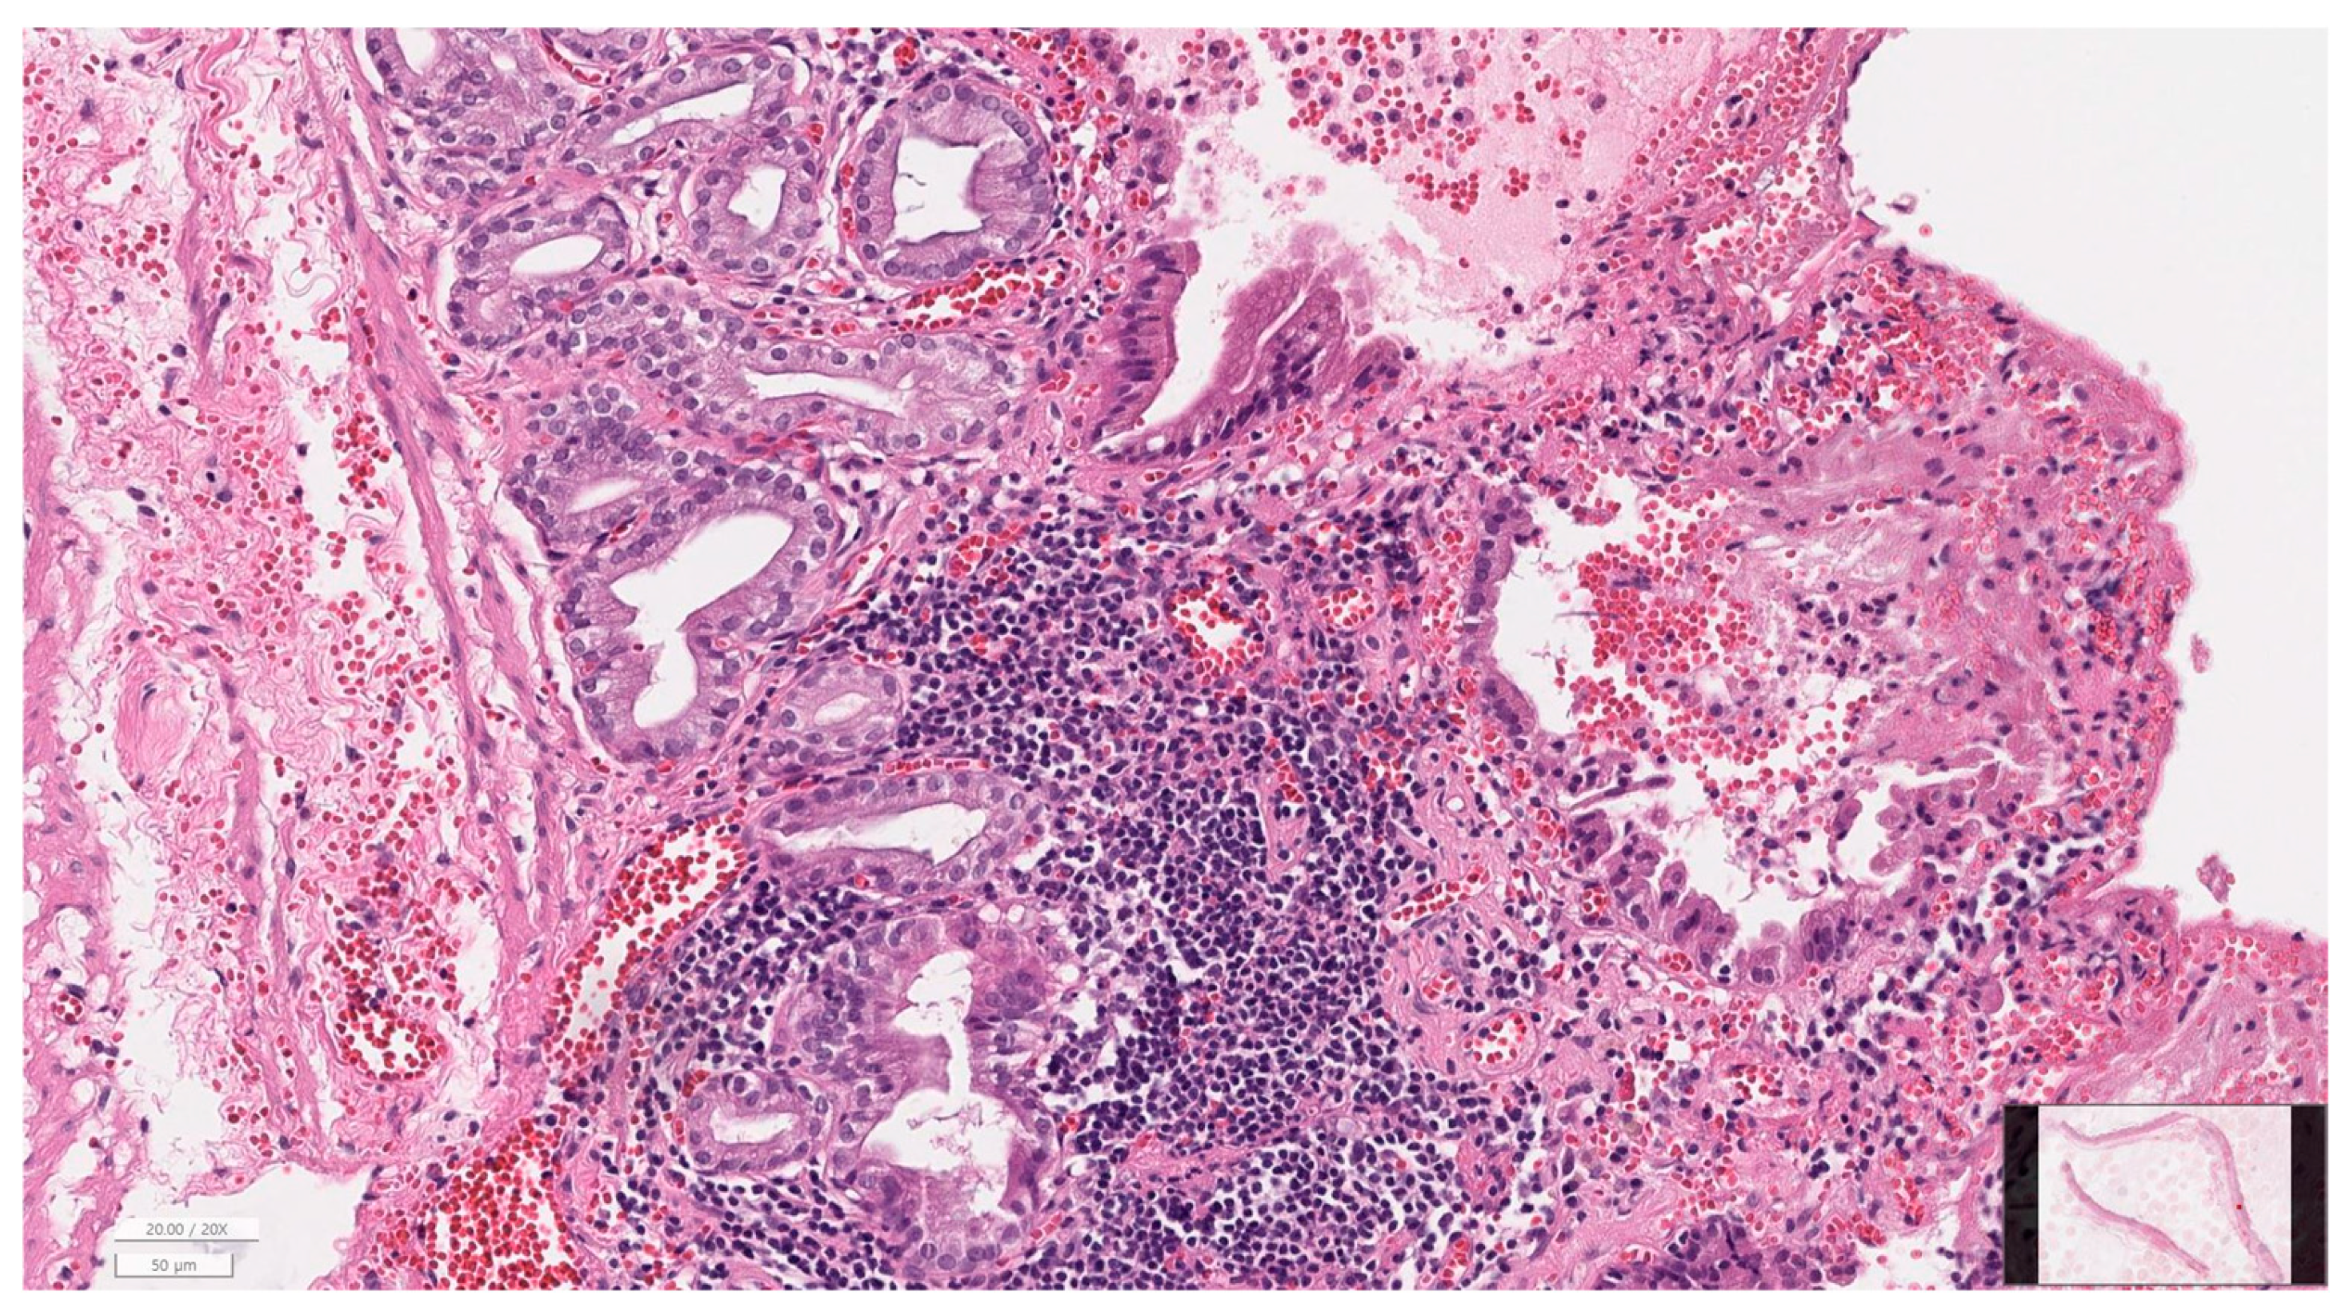

2.7. Histopathological Evaluation

3.6. Histopathology of Gallbladder and Liver

| Inflammation | None | 17 (32.7) |

| Mild | 22 (42.3) | |

| Moderate | 10 (19.2) | |

| Severe | 3 (5.8) | |

| Fibrosis | None | 44 (84.6) |

| Mild | 7 (13.5) | |

| Moderate | 1 (1.9) | |

| Mucosal hyperplasia | Present | 47 (90.4) |

| Bacteria on histology | Present | 0 (0.0) |

| Perforation | Present | 1 (1.9) |